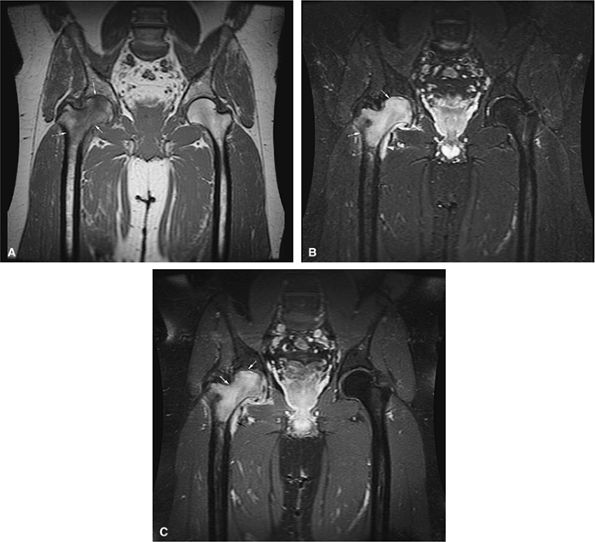

FIGURE 13.18 ● In chronic myelogenous leu-kemia, diffuse marrow involvement infiltrates regions of previous red marrow stores in the femurs (curved arrows) and acetabulum (straight black arrows) and demonstrates low signal intensity on a T1-weighted image (A) and high signal intensity on a corresponding STIR image (B). The sites where yellow marrow is spared (the greater trochanter and femoral epiphysis) demonstrate high signal intensity on the T1-weighted image and low signal intensity (from the nulled fat signal) on the STIR sequence (white arrows).

In the acute phase of chronic leukemia, particularly in chronic myelogenous leukemia patients in blast crisis, there is almost complete replacement of both red and yellow marrow areas. The decreased signal on T1-weighted sequences represents replacement of marrow fat by tumor cells, which have a significantly longer T1 relaxation time. On STIR images, tumor cells appear as areas of white on a black or gray background (Fig. 13.19).

Severe anemias or other marrow-invasive processes may have a similar MR appearance. Multiple myeloma is more variable but is generally less symmetrical, more patchy, and irregular in distribution.55,56